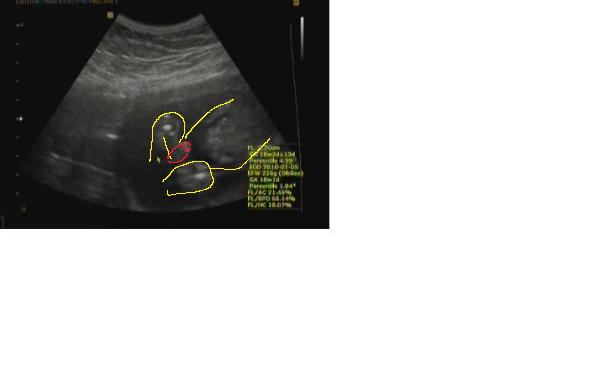

Bogi, jó lehetett az UH

Twist, elismerésem, hogy kibírod, hogy nem rohansz el 4D-re. Mi is úgy terveztük, hogy együtt tudjuk meg, de a dokim csinált egy soron kívüli UH-t, és ott megmondta. Én meg nem bírtam ki, és rögtön felhívtam apát a nagy hírrel